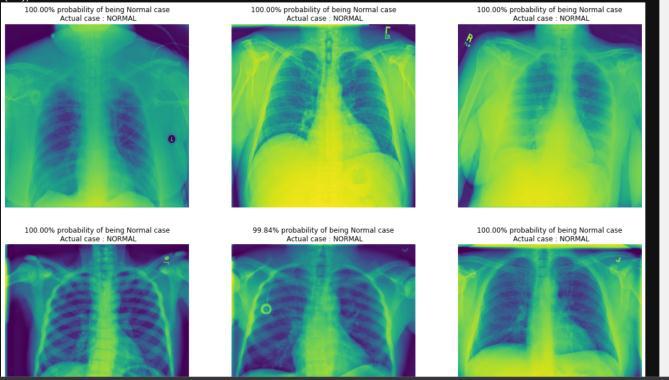

VI. RESULT & DISCUSSION

Theresultsofthecloud-basedwebapplicationforrapid andprecisedetectionoftuberculosisusingSupportVector Machine (SVM) can be evaluated based on the accuracy, precision,recall,andF1-scoreoftheTBdetectionmodel.

The accuracy of the TB detection model measures the proportion of correctly classified TB-positive and TBnegative samples out of all test samples. A high accuracy scoreindicatesthatthemodelisabletoaccuratelyclassify TB-positiveandTB-negativesamples.

Precision measures the proportion of true TB-positive cases out of all positive predictions, whilerecall measures the proportion of true TB-positive cases out of all actual TB-positivecases.Ahighprecisionscoreindicatesthatthe modelisabletoaccuratelypredictTB-positivecases,while a high recall score indicates that the model is able to correctlyidentifyallTB-positivecases.

The F1-score is the harmonic mean of precision and recall, and provides a single score that takes both metrics into account. A high F1-score indicates that the model is bothaccurateandreliableinpredictingTB-positivecases.

Overall, the cloud-based web application for rapid and precise detection of tuberculosis using SVM can provide a valuable tool for healthcare providers to quickly and accurately identify TB-positive cases and initiate appropriate treatment. The application can help to reduce the burden of TB on global health and improve patient outcomesbyfacilitatingearlydetectionandtreatment.

Fig–6ResultGenerationinbulkfiles

Fig 7ReportGenerationinGraphGeneration Fig–8ResultGenerationin100%detection

photos by image modality and anatomic location after converting them to JPEG (Joint Photography Experts Group) format. In both the validation and test sets, we achievedoutstandingoverallclassificationaccuracy(>99.5 percent). The collected results allow us to assess the viability of the methods adopted. It also allows us to identify the best classification scenario and machine learning method to carry out the classification of radiographswithandwithouttuberculosis.